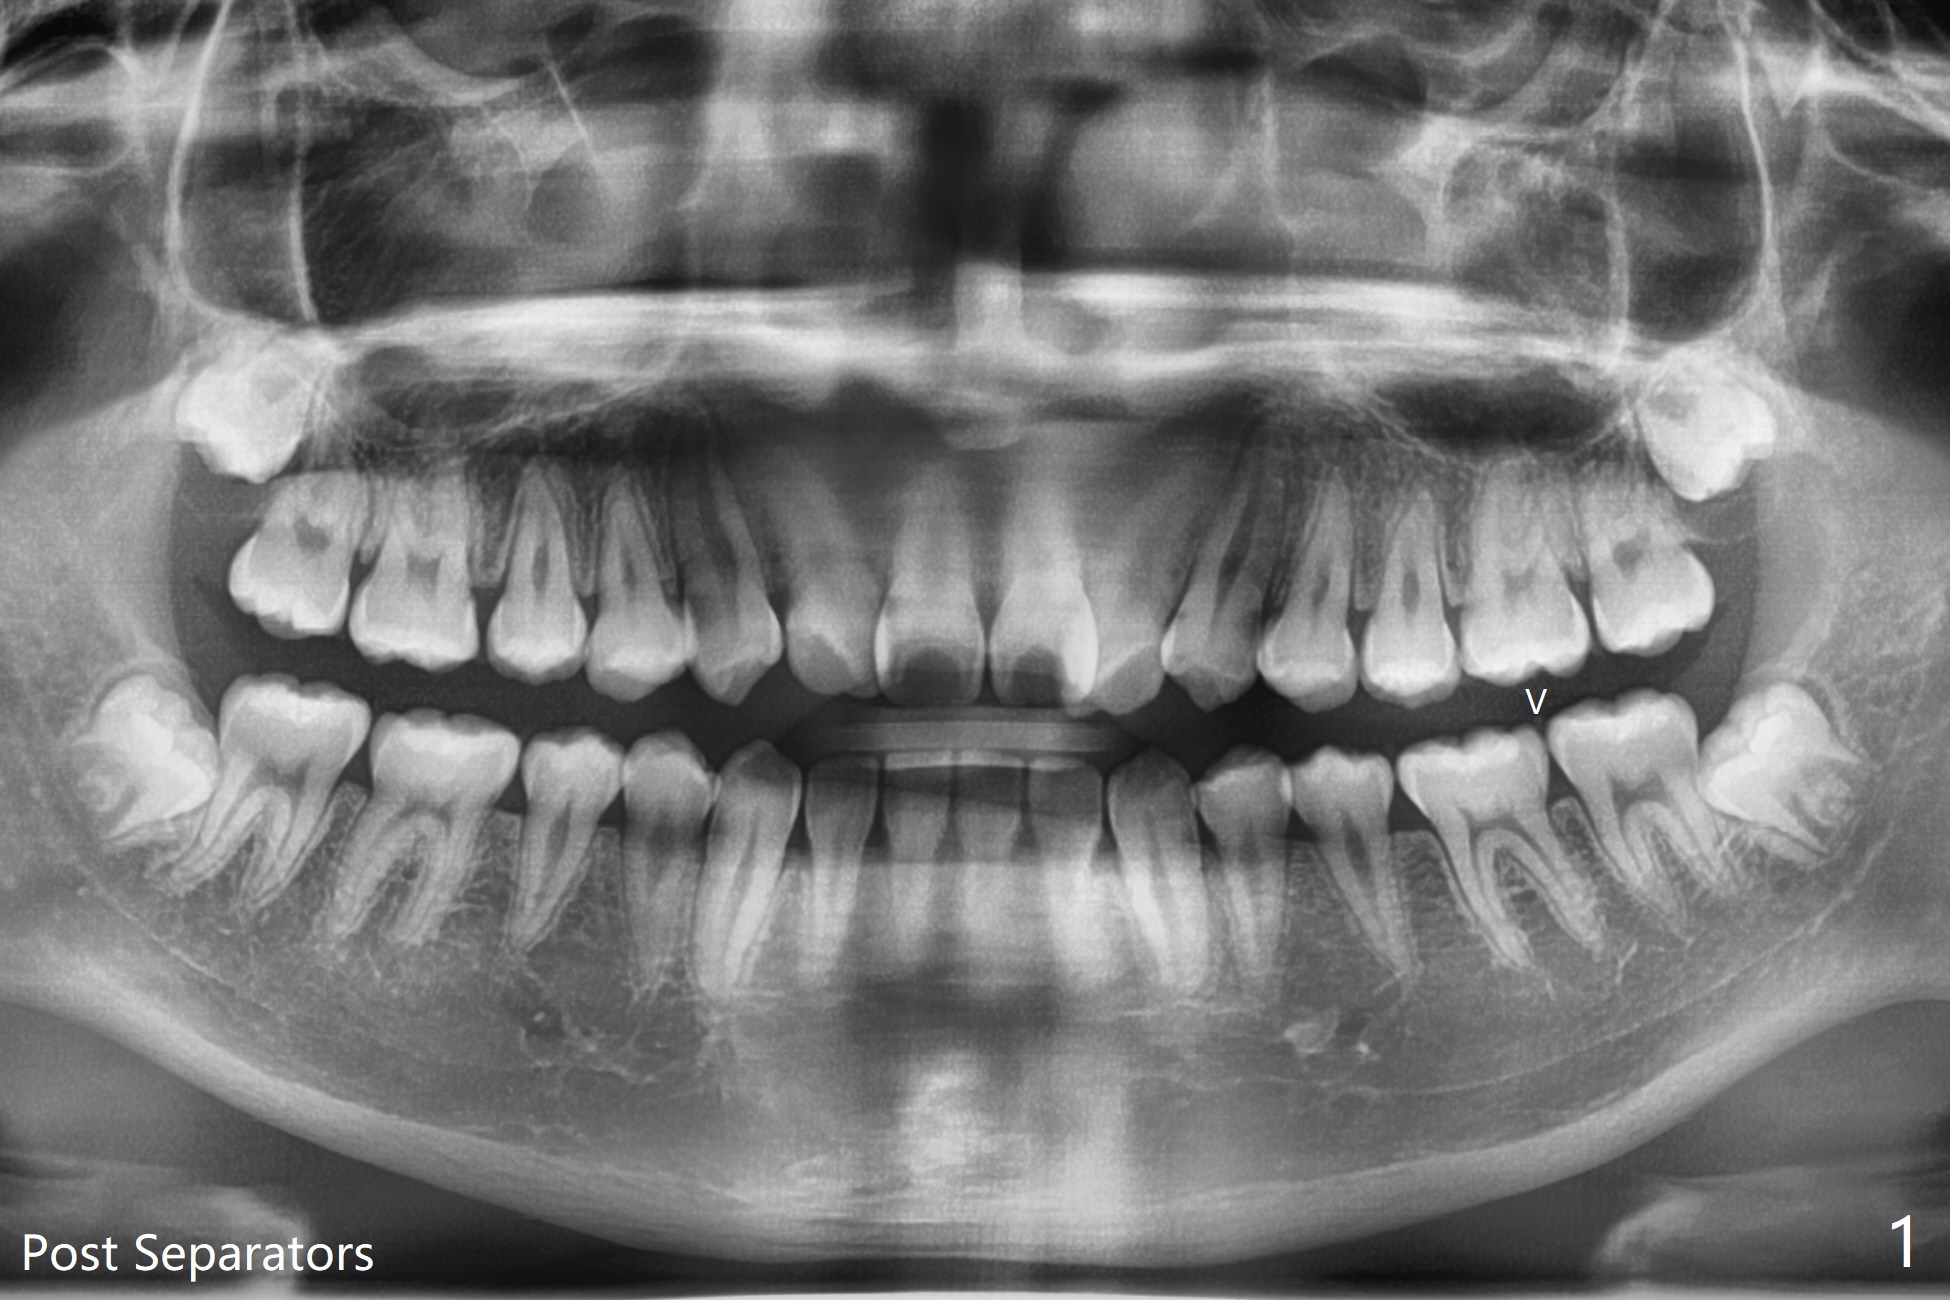

15岁男孩分离器使用后(图一:箭头)无法在左下7放置band,可能因为8阻生(图一,与图二对比)。1.5年后左下8萌出(图二),下颌8拔除,牙槽窝放置Osteogen Plug(图三),八个月后牙槽窝愈合(图四)。